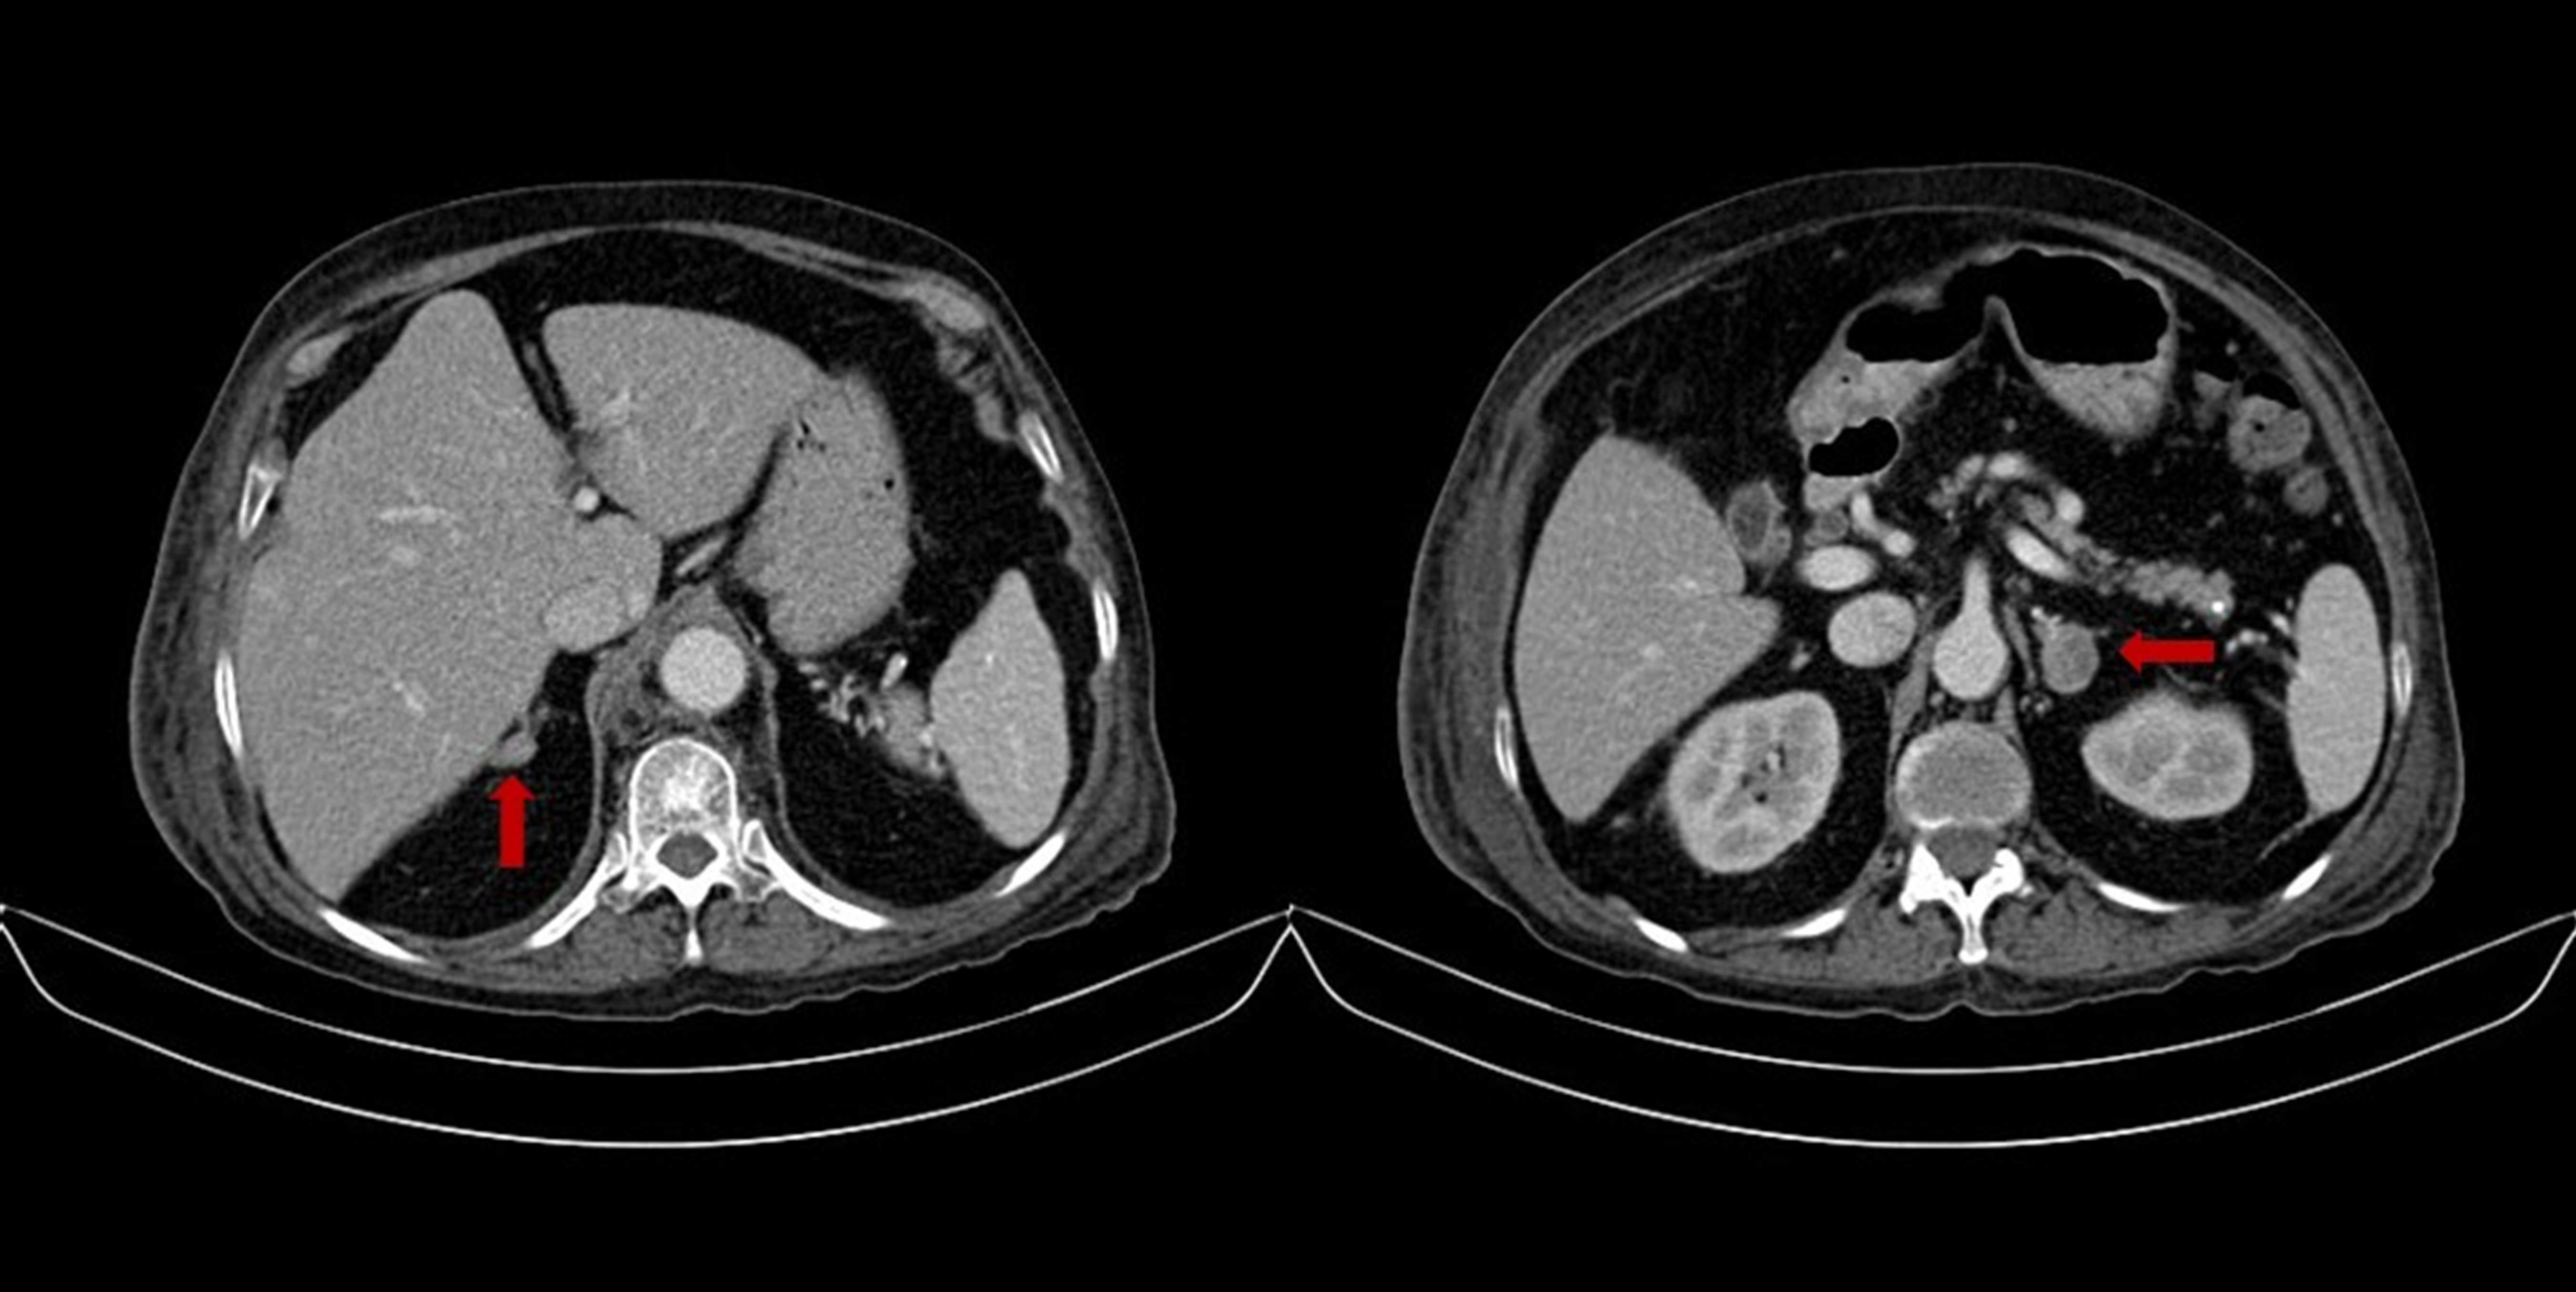

Figure 1.

Abdominal tomography. Right adrenal nodule 14x9 mm and left adrenal gland nodule 23x18 mm

A 76 years-old woman with history of controlled hypertension (with losartan and amlodipine) presented to our hospital referring weight loss of 4 kg in two months, edema that progressed to anasarca and back lumbar pain. Besides the edema her physical examination was completely normal with no clinical signs suggestive of hypercortisolism. Among the studies requested, an abdominal tomography showed a right adrenal gland nodule of 14x9 mm and another one in the left adrenal gland of 23x18 mm (Fig. 1), additionally multiple vertebral fractures were reported. As part of the study of adrenal adenomas the patient had an abnormal value of cortisol after a low dose suppression test with dexamethasone (13.3 µg/dL (normal value: <1.8 µg/dL), with a normal value of free urinary cortisol and her potassium was low (she was not on diuretics). The results of the patient laboratory test are shown on Table 1.